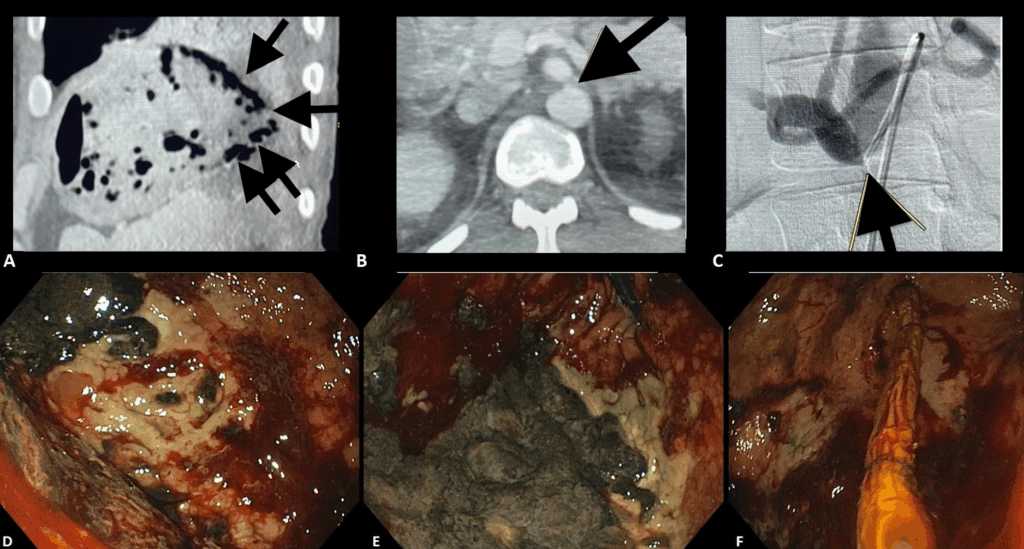

Figura 2 Adaptado de Dall’Agnol et al (9):

A: Tomografia abdominal com pneumatose da parede gástrica (setas).

B: Angio-TC demonstrando estenose do Tronco celíaco (seta).

C: Arteriorgrafia confirmando estenose do Tronco celíaco (seta).

D: Úlcerações extensas e tecido necrótico com sangramento difuso no corpo gástrico.

E: Tecido necrótico extenso no fundo gástrico.

F: Passagem da sonda de Terapia Endoscópica a Vácuo (1a sessão).